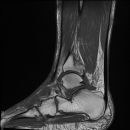

Talus Fraktur

Snowboard fracture Talus